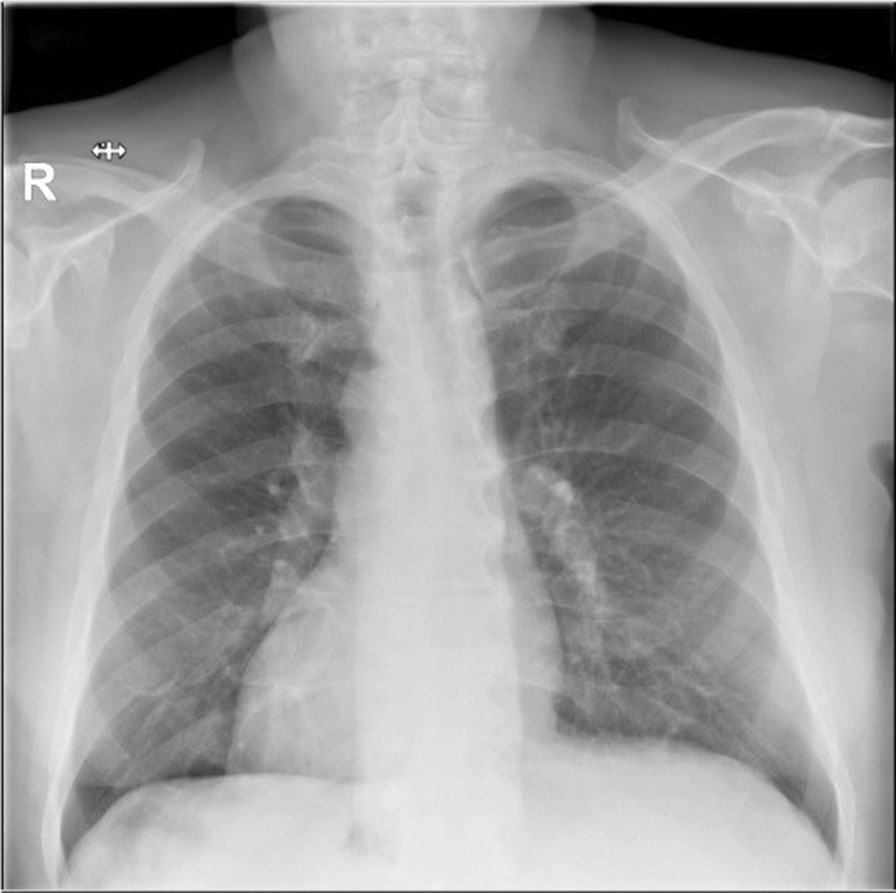

Chest X-ray of the patient with dextrocardia